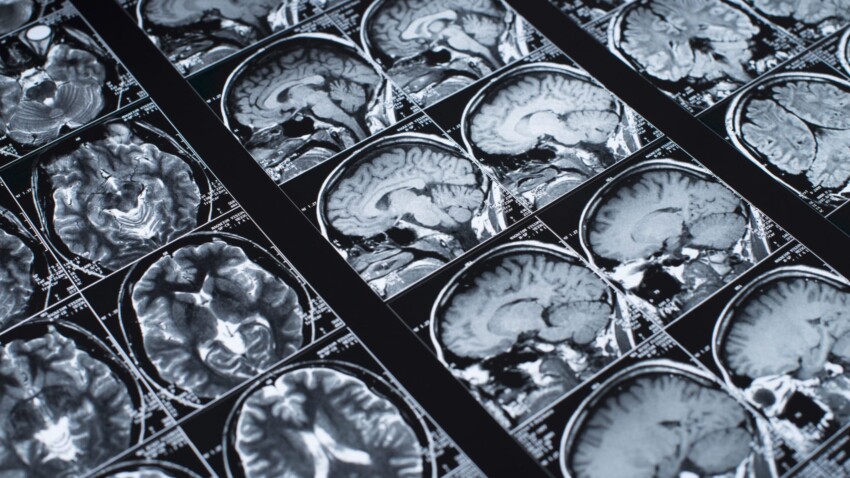

Io però non mi sentivo tranquillo e gli ultimi malesseri mi avevano lasciato nella testa il pensiero che dovevo approfondire di più quello che mi era successo. Visto che nella vita sono molto scrupoloso e mi piace andare fino in fondo nelle cose decisi di andare privatamente a fare una risonanza magnetica con liquido di contrato. Il referto mi spiazzò e mi mandò in crisi così come non mi era mai capitato in vita mia “pregressa ischemia talamica sinistra”.